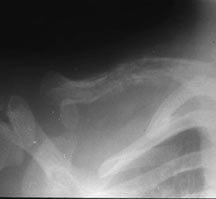

- May arise from any bone and any site within a bone (epiphyseal, metaphyseal, diaphyseal)

- Radiographically variable appearance: may appear benign (geographic) or malignant (permeative or moth eaten)

- Pelvis

- Humerus